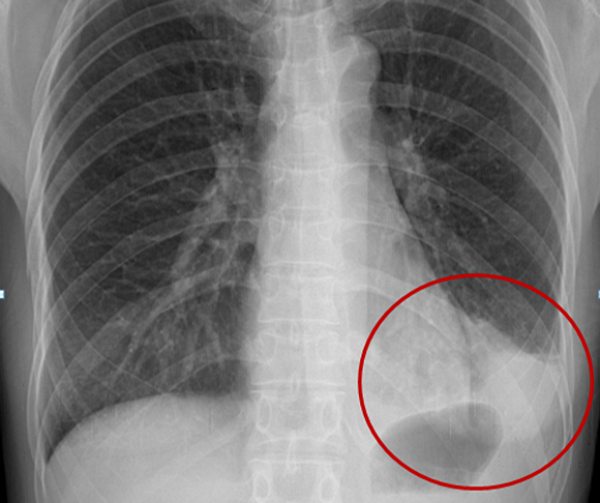

폐렴은 임상적인 증상과 X-RAY 검사를 통해 진단이 가능하다. 폐렴으로 진단되면 환자의 중증도나 사망 위험도에 따라 입원 치료 여부를 결정해야 한다. 특히 노년층의 경우 다른 질환들이 동반하는 경우가 많아 긴 회복 기간이 필요하다.